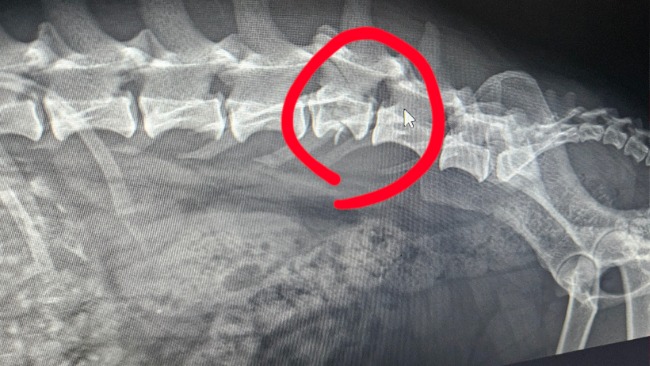

Dziś udało się nam dotrzeć do chirurga i wykonać zdjęcia RTG, diagnoza: złamany kręgosłup.

Maja słabo porusza tylnymi łapkami, ale ma głębokie czucie w obu, a lewą łapką potrafi odwodzić. To daje nadzieję! Wszystkie funckxe fizjologiczne są zachowane. Dodatkowo ogromnym atutem jest szybki czas reakcji po wypadku – dzięki temu szanse na powrót do sprawności są naprawdę duże.